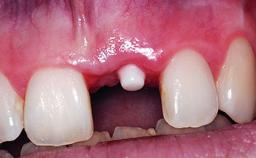

Replacement of a Compromised Upper Right Central Incisor: Hard- and Soft-tissue Augmentation, Late Placement of an RC Bone Level Implant

A 36-year-old male patient with a compromised maxillary central incisor was referred by his general dentist for consultation. The patient’s chief complaints were the gradual debonding of a temporary crown on the right central incisor and unsatisfactory esthetics due to an increasing diastema between the right central and lateral incisors. The patient reported a traumatic event some years previously, when a crown had been placed after root-canal treatment. The referring dentist wanted to provide a new crown restoration, but was concerned about the condition of the residual root. Anamnesis was negative for any other dental or periodontal pathology in the remaining dentition. The patient reported taking no medications: He was a smoker (10 to 15 cigs/day) and had realistic esthetic expectations.

Soft Tissue Grafting Simultaneous

Soft Tissue Contour and Volume Slightly compromised